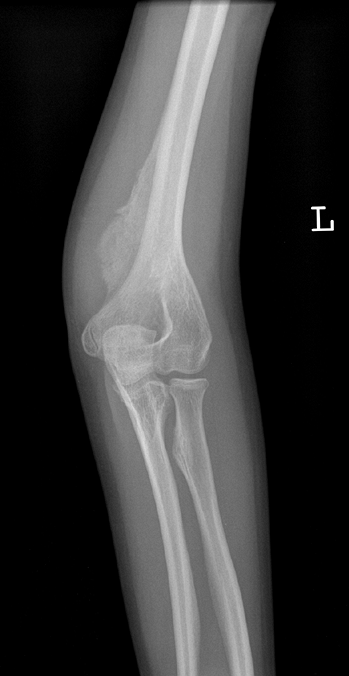

![]() |

Figure 7.11

Osteogenesis imperfecta (OI). This olecranon avulsion in a 14-year-old boy with type 1 OI was treated with stable internal fixation and early return to motion. Olecranon avulsions are frequently associated with a diagnosis of OI. |